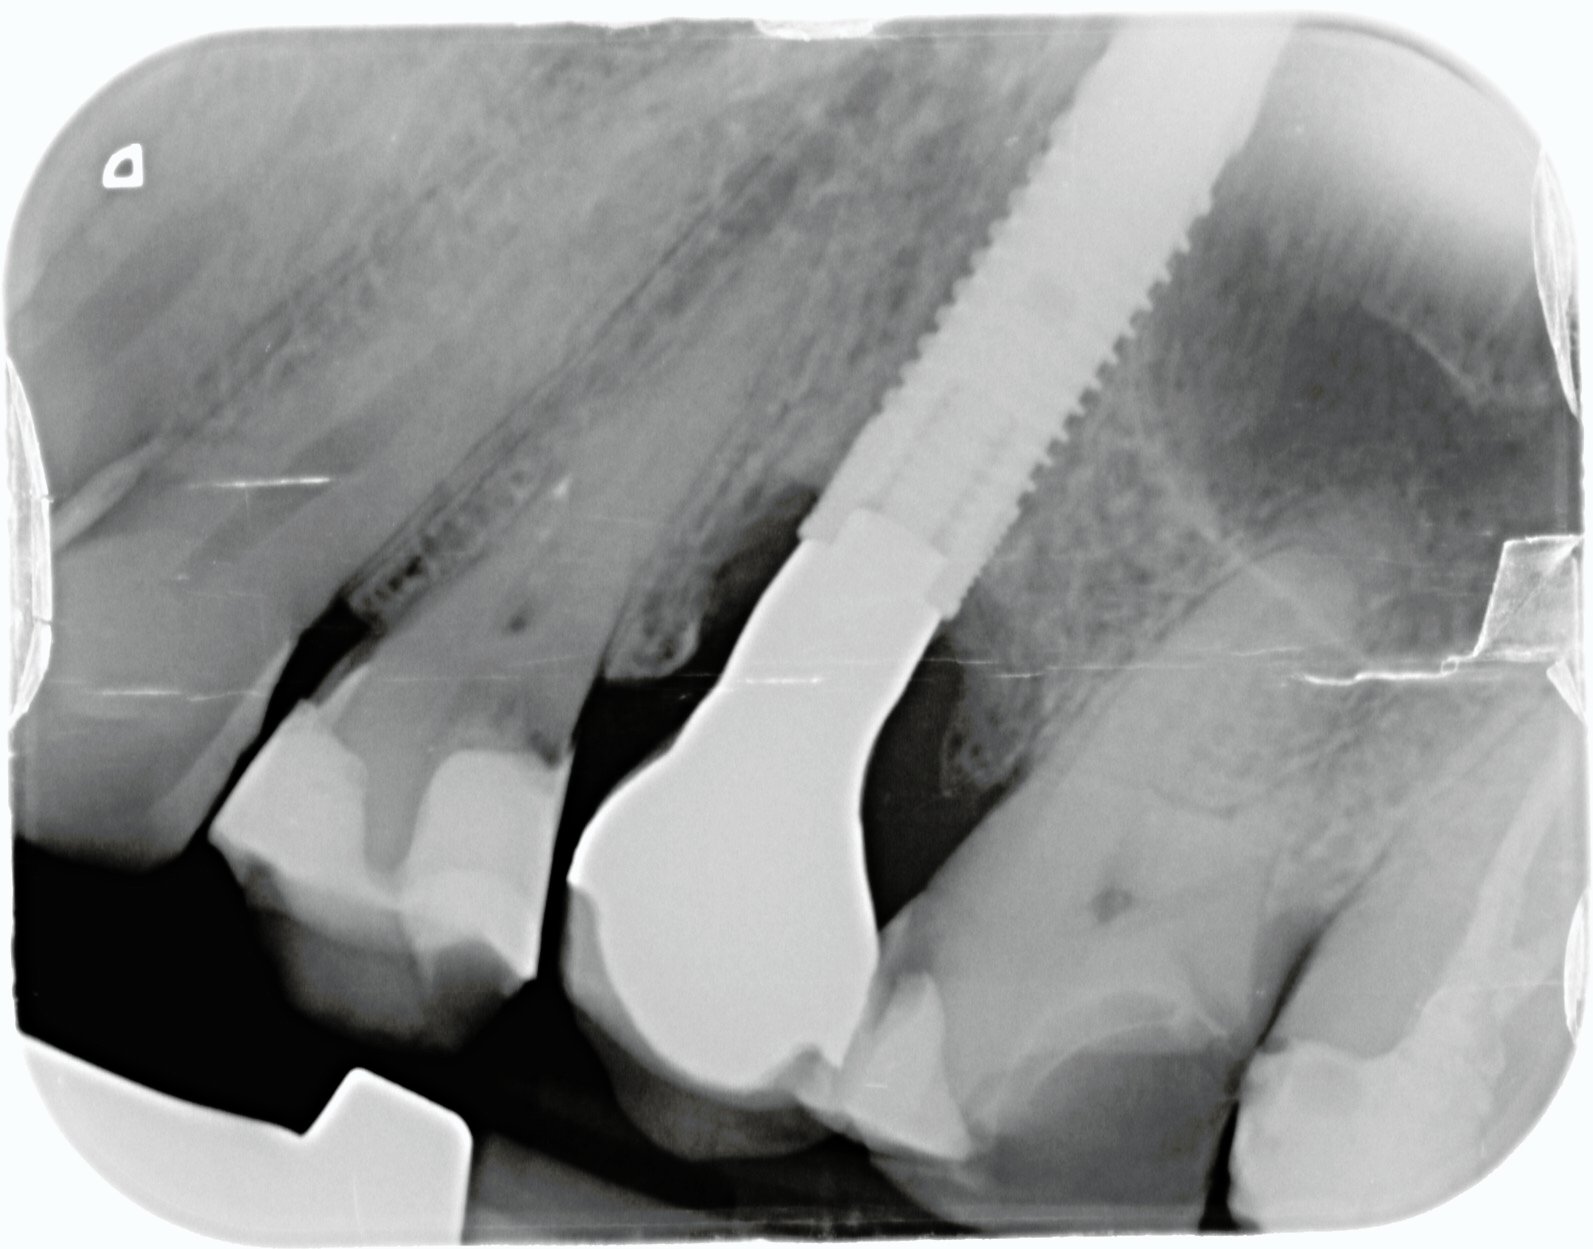

Hola. Enhorabuena en primer lugar por vuestra web, es una idea fantástica. Me animo a mandaros mi primer caso, es un implante que lleva un paciente y necesito saber la [...]

El paciente presenta movilidad en la corona del 25, y necesitamos saber de qué tipo de implante se trata para poder solicitar el instrumental necesario, ya que no quiere volver [...]